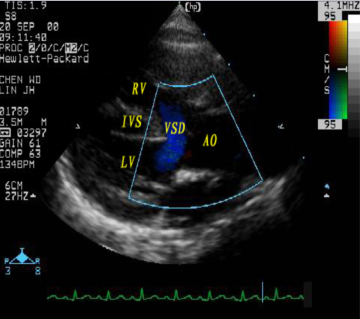

法洛四联症:超声心动图表现

室间隔缺损、主动脉骑跨

右室流出道狭窄

连续波多普勒测量右室流出道压差